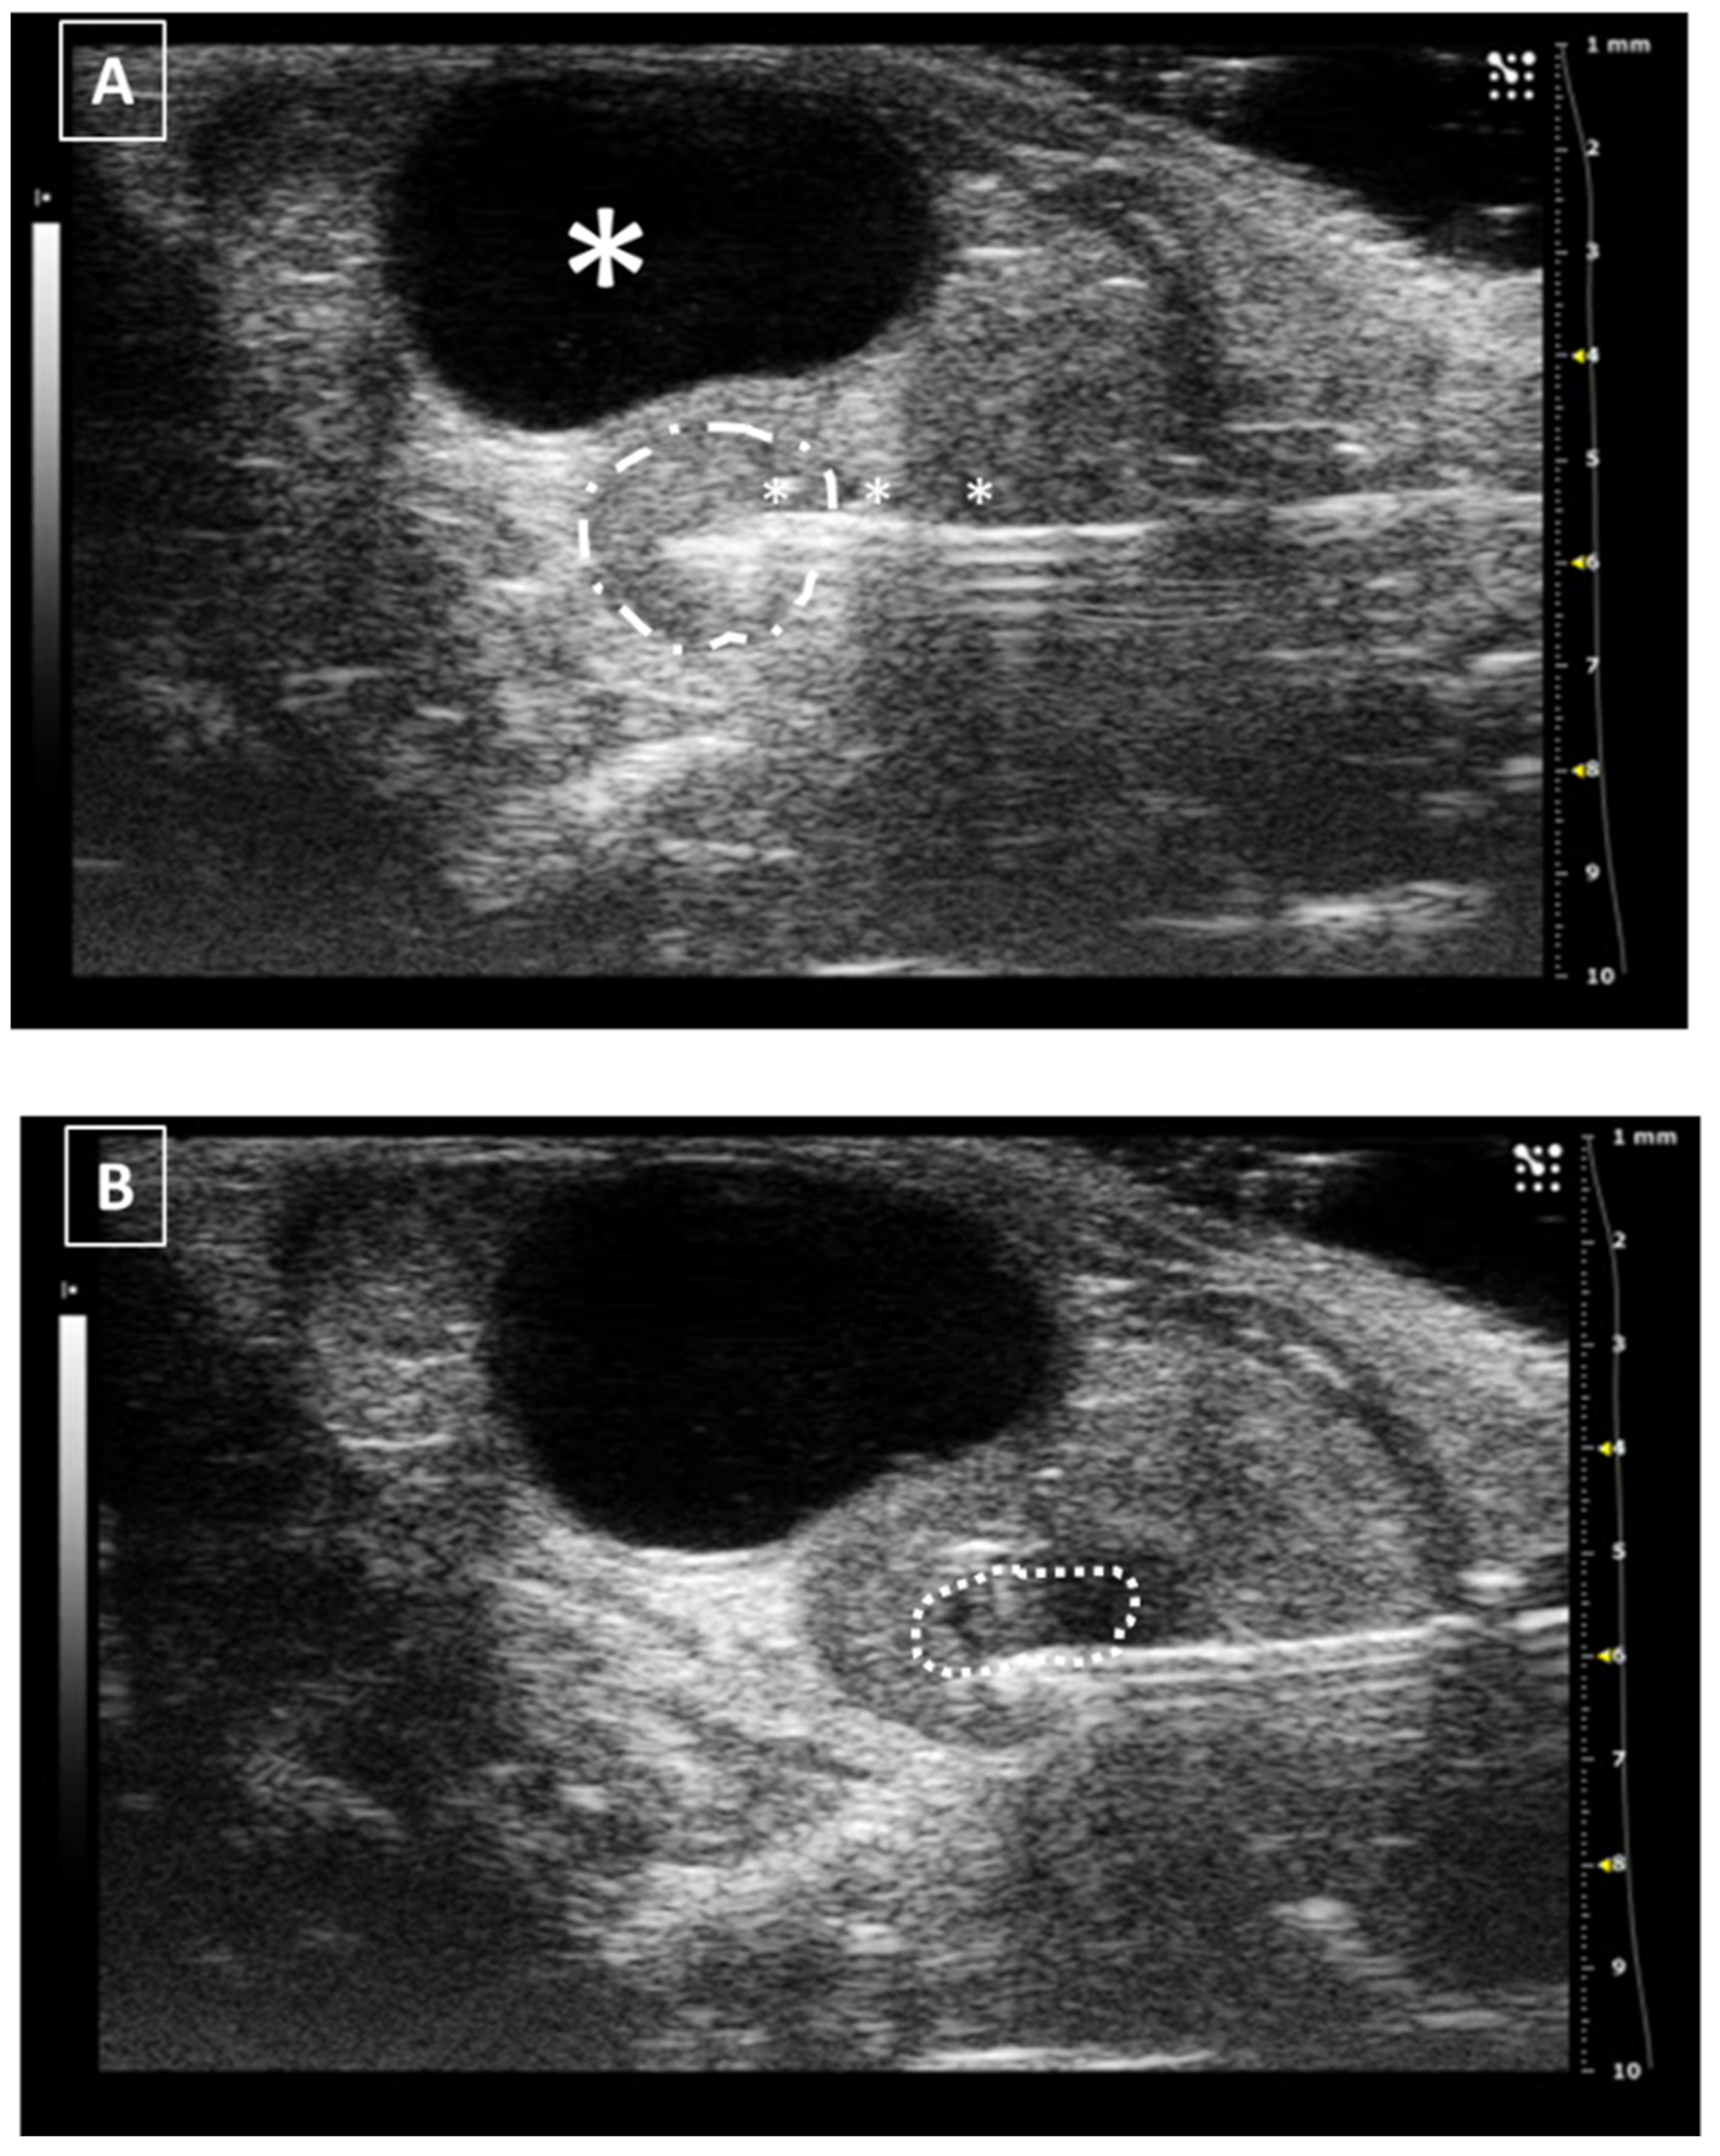

The intrahepatic injection is an easy procedure due to the size of the liver, which allows us to inject in both left and right sides of the organ. In our opinion, the right approach is easier due to the presence of the stomach on the left, which reduces the space for maneuvering. The animal is placed in ventral recumbency and hair is shaved in the cranial part of the abdomen. After localizing the desired region of the liver, the needle is moved under and parallel to the probe from the outside and into the abdomen, avoiding the rib bones. We will see a hyperechoic line going into the hypoechoic and homogeneous hepatic tissue. The injection can be confirmed with the appearance of an anechoic structure (the injected fluid) inside the liver tissue. After injecting, the needle should be kept in place for some seconds. Later, it can be removed and the organ should be examined for the presence of hemorrhages. An example of a liver injection is shown in Figure 4.

The recommended maximum volume of injection depends on the size of the organ, but in the literature, we can find volumes around 40–50 microliters [28,29,30]. An excess in the injection volume could lead to a rupture of the hepatic tissue due to a pressure increase in the tissue and this will lead to the appearance of an acute local hemorrhage, or even an hemoabdomen in case the rupture affects the Glisson’s capsule.

3.4. The Spleen

The spleen is a hypoechoic hematic organ, typically located on the left side of the abdomen, caudal to the stomach and lateral to the left kidney, but it can slide around the cranial part of the abdomen, especially during splenomegaly [25,26]. Due to this reason, the approach for its injection will depend on where it is located. In its usual place, a lateral approach is the best and easiest way of injecting. The animal should be placed in lateral recumbency, with the left side up. After shaving the hair, the scanning probe is placed over the last ribs and slowly displaced caudally. The spleen will appear on top of the screen, just under the skin. We will slightly balance the probe ventrally without losing sight of the structure and will insert the needle from the back of the animal. In a standardized view, the needle will arise from the right side of the screen and go medially. If the pressure from the ultrasound probe is enough, the spleen will be immobilized between it and the needle, and the injection will be performed easily. Similar to the liver, the maximum injected volume depends on the organ size but in previously published work we can find a range from 20 to 50 microliters [31]. After a few seconds, the needle can be removed and a last exam for the absence of bleeding should be performed. A representative image of the injection is shown in Figure 5.

Figure 4. Intrahepatic injection. (A) Right side approach. Needle is marked with white asterisks. (B) Left side approach. Injected fluid is marked with white arrows. The fluid appears as an anechoic collection inside the homogeneous hypoechoic liver tissue. Images obtained at 40 MHz frequency.

Figure 5. Intrasplenic injection. Needle is marked with white asterisks and the spleen is surrounded by a dashed line. Stomach can be localized due to its typical acoustic shadow. Images obtained at 40 MHz frequency.